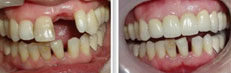

部分小孩到了换牙期时,恒牙已经萌出,乳牙却依然没有脱落。这些滞留的乳牙占据了正常牙列的位置,使得恒牙错位萌出,引起牙列错乱,因此滞留的乳牙必须拔除。

总得来说: 滞留的乳牙越早拔除越好,否则引起恒牙错位萌出后需要对错乱的牙列进行矫正,不仅痛苦,而且增加费用。